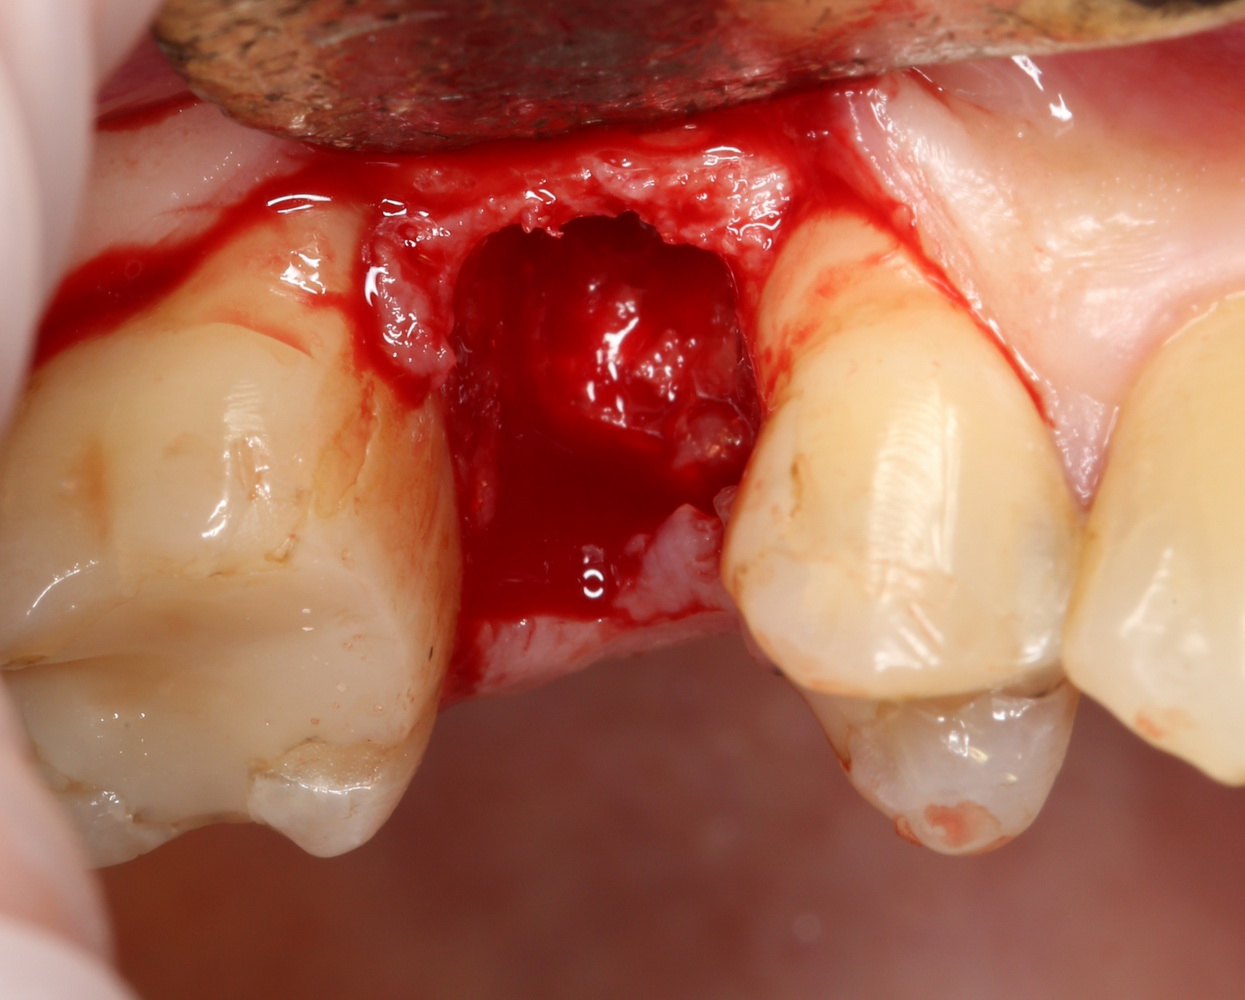

Для удаления зубов мы используем прямой элеватор и тонкие «корневые» щипцы-байонеты. Сама процедура удаления занимает около 10 минут:

Давайте внимательно посмотрим на состояние лунок центральных резцов после удаления:

Приемлемый фенотип (сочетание толщины и ширины участка жевательной десны) — это, конечно, приятно. Но гораздо важнее сосредоточиться на рисках, их на этот момент два:

— травматическое повреждение слизистой, вызванное удаление зубов связано с тем, что при хроническом воспалении слизистая оболочка теряет эластичность, поэтому легко рвётся. Такая ситуация создаёт серьёзную угрозу эстетическому результату лечения, в зависимости от того, насколько быстро десна придёт в норму.

— как и предполагалось после КЛКТ, утрата костной стенки привела к тому, что десна провалилась в просвет лунки левого центрального резца. Это еще больше усугубляет клиническую ситуацию.

Для нас это не было неожиданностью. Зная закономерности изменений тканей при хроническом  воспалении и данные КЛКТ, мы можем довольно точно предсказывать развитие клинической ситуации и соответственно к ней подготовиться. Именно поэтому, помимо обычной немедленной имплантации, мы запланировали аугментацию лунки с помощью биоматериалов и метода трансплантации лоскута (см. предварительные планы лечения).